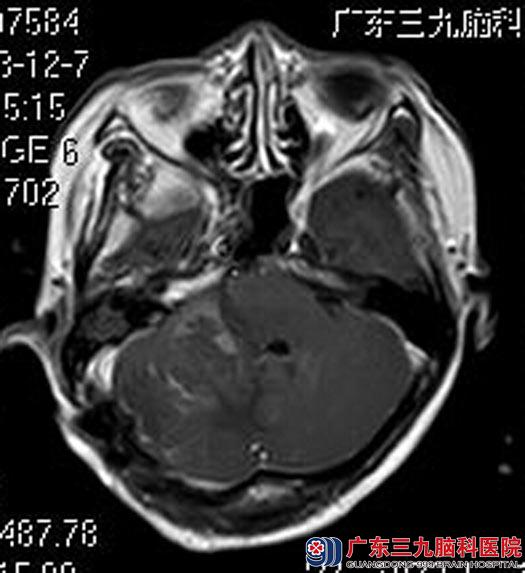

由鲁明主任主刀,在全麻下行经乙状窦后入路行右侧桥小脑角占位性病变切除术,术中见肿瘤位于右侧桥小脑角,黄白色,囊实性,质中,予显微镜下电凝分块切除,成功进行了分离,右侧听神经、面神经、三叉神经、舌咽神经保护完好。术后,黄女士没有出现手术并发症,已康复出院。

术后